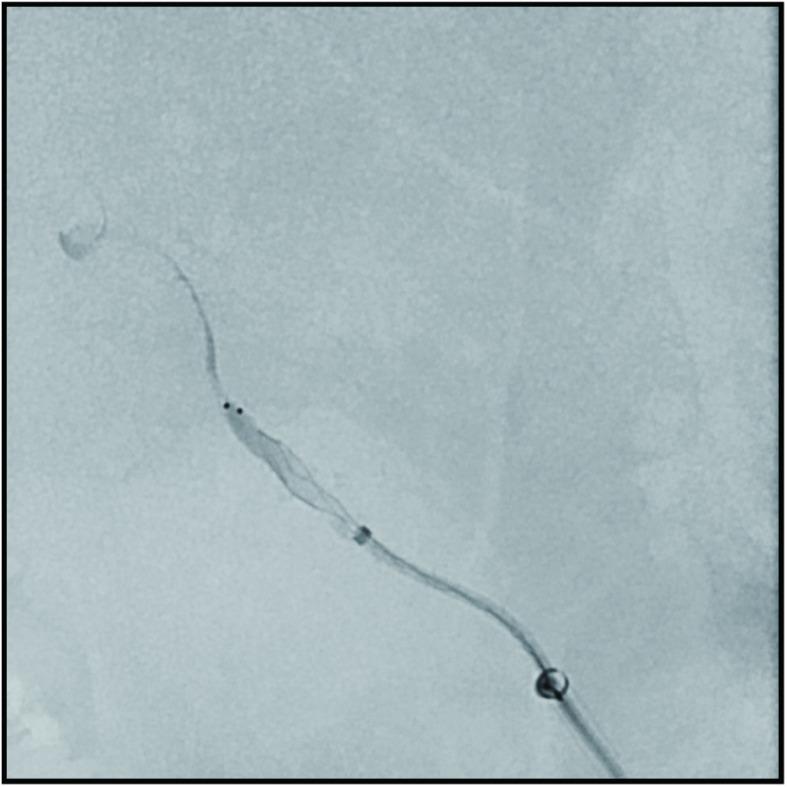

An 82-year-old female who had undergone a mitral valve annuloplasty developed sudden aphasia, right hemiplegia, and right unilateral spatial neglect on postoperative day 10. Cranial MRI indicated occlusion of the horizontal segment of the left middle cerebral artery. During mechanical thrombectomy, a vasospasm snagged the stent, and re-sheathing attempts failed repeatedly. We wedged the microcatheter into the spasm site and slowly injected a solution containing 1 cc of nicardipine, 2 cc of contrast medium, and 2 cc of heparin in normal saline intra-arterially. After several minutes, we retracted the Trevo wire slightly and easily removed the stent. The thrombus adhered to the retrieved stent. Post-retrieval imaging showed that the branch was completely recanalized.

In cases wherein a microwire or stent retriever becomes difficult to remove, we propose switching to a microcatheter with a sufficient diameter to allow vasodilator injection. If the microcatheter is difficult to remove, our method can be utilized by severing the hub, inserting a larger-bore catheter, and injecting vasodilators. Adding contrast medium to the intra-arterial injectate allows visualization of whether the solution has reached the spasm site. Furthermore, by injecting the solution through the wedged catheter, pooling of the solution at the spasm site can be confirmed.

一名82岁女性,曾接受二尖瓣环成形术,术后第10天突然出现失语、右侧偏瘫和右侧单侧空间忽视。头颅MRI显示左侧大脑中动脉水平段闭塞。在机械取栓过程中,血管痉挛卡住了支架,多次尝试重新收回支架均失败。我们将微导管楔入痉挛部位,并经动脉缓慢注射一种溶液,该溶液包含1毫升尼卡地平、2毫升造影剂和2毫升肝素溶于生理盐水中。几分钟后,我们稍微回撤Trevo导丝并轻松取出了支架。血栓附着在回收的支架上。取栓后成像显示分支完全再通。

在微导丝或支架回收器难以取出的情况下,我们建议换用直径足够大以允许注射血管扩张剂的微导管。如果微导管难以取出,可通过切断导管座、插入更大口径的导管并注射血管扩张剂来采用我们的方法。在动脉内注射剂中添加造影剂可观察溶液是否到达痉挛部位。此外,通过经楔入的导管注射溶液,可以确认溶液在痉挛部位的聚集情况。